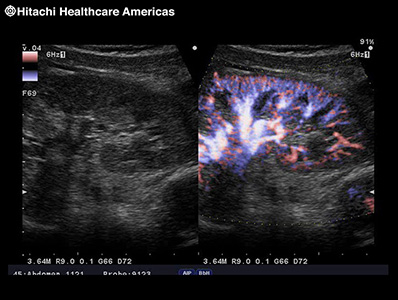

Directional eFLOW (D-eFLOW)

Displays blood flow with directional information at higher frame rates and spatial resolution compared to conventional methods. Detail and accuracy of blood flow information is greatly increased with reduced blooming of color.

Dual CF

Real-time side-by-side display of a B-mode image and Color Doppler image assisting in easy anatomical interpretation of blood flow.